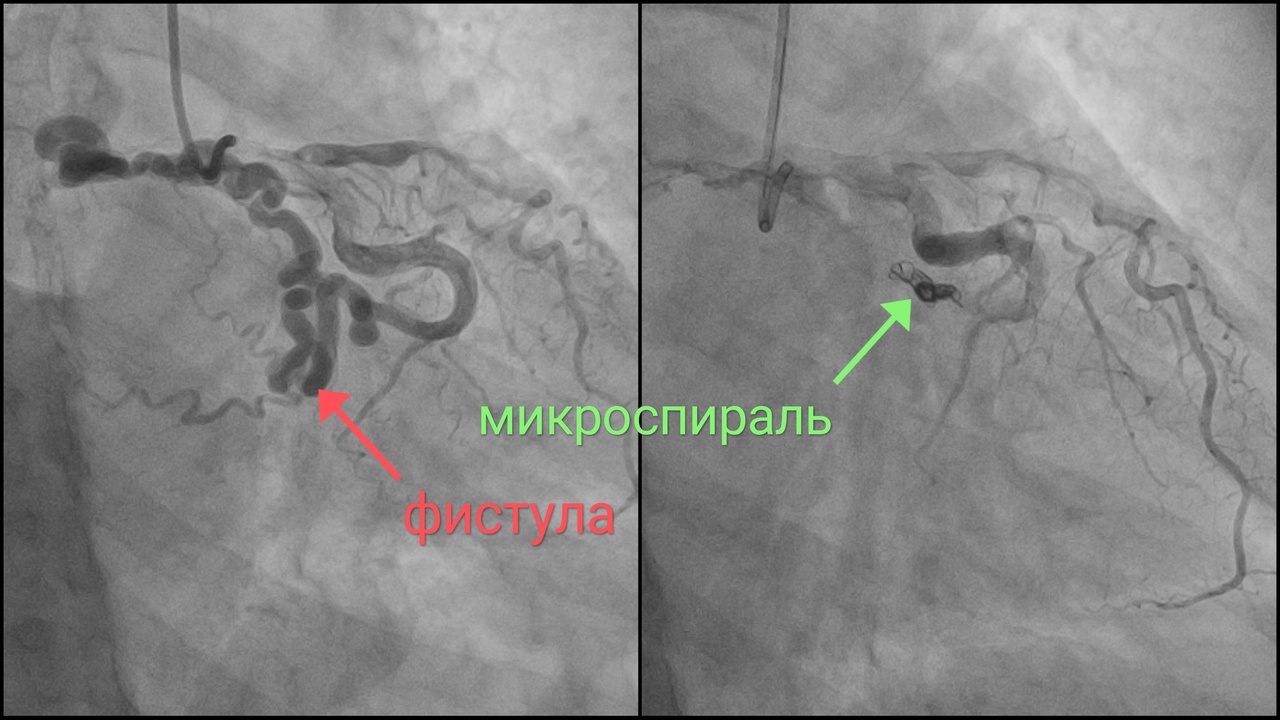

Медики регионального сосудистого центра осуществили уникальную хирургическую операцию на сердце. Её официальное название «эмболизация коронаро-легочной фистулы».

Как нам удалось узнать из пояснений специалистов, фистулой называется патологический канал (другое название «свищ») — в данном случае между коронарной артерией и легочным стволом. Эмболизация, говоря по-русски, есть закупорка канала специальными эмболами.

«Данная аномалия выявляется всего лишь у 0,002% людей, — сообщил и.о.руководителя Регионального сосудистого центра Евгений Ким, — Пациентку беспокоили периодические боли за грудиной, обследование подтвердили ишемию миокарда и выявили увеличение правого предсердия, что косвенно свидетельствовало о перегрузке в малом круге кровообращения. Был выявлен патологический сосуд больших размеров, из-за которого возник “синдром обкрадывания” — недостаточный кровоток в сосудах сердца. Сама же фистула была сильно извита и имелись признаки высокого давления в ней и истончении стенки, что создавало высокий риск разрыва и внутреннего кровотечения».

В ходе операции новгородские медики малоинвазивным способом с помощью специальных катетеров дошли до сердца и разместили в патологический сосуд эмболу — специальные имплант, перекрывающий кровоток. Так желаемый результат был достигнут.